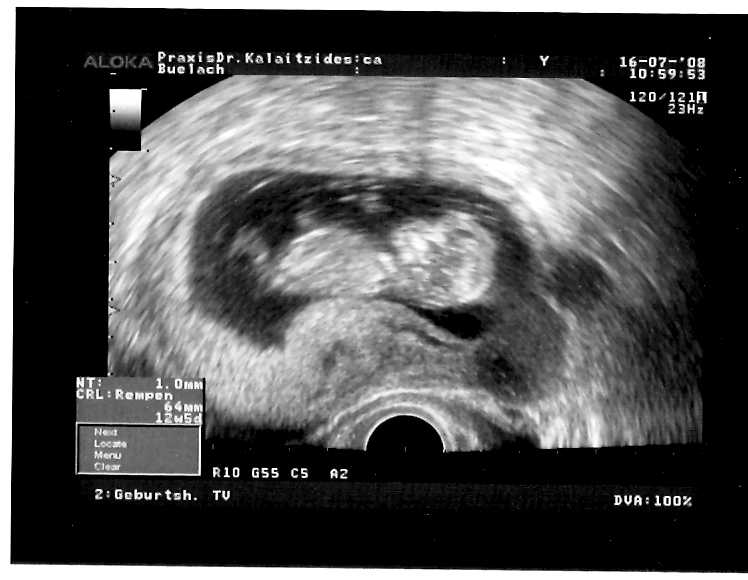

Unser Gummibärli ist nun ein Würmli und schon 65mm gross (13. Schwangerschaftswoche)

Unser Gummibärli beim ersten Ultraschall in der 9. Schwangerschaftswoche